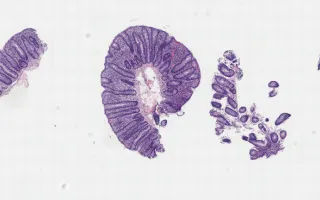

A 66 year-old female with 2-3 months diarrhoea, weight loss with nausea and vomiting.

Iatrogenic effects on the GI tract are an extremely interesting but under-recognized entity that often masquerade as celiac sprue and/or autoimmune enteropathies. One of the recently described entities is the olmesartan-associated enteropathy caused by anti-hypertensives class of Angiotensin receptor (ARB) blockade drugs. Olmesartan enteropathy patients often presents with diarrhea, weight loss, nausea and vomiting.

Characteristic histologic findings are abundant intraepithelial lymphocytes in the duodenum, stomach, and colon. In addition, there is mild to moderate active (i.e. neutrophilic) inflammation. Associated findings in the small intestine are villous atrophy/distorted villi, increased sub-epithelial collagen and extensive crypt dropout. The large intestine shows crypt architectural distortion, crypt abscess, consistent with chronic active colitis and suggestive of inflammatory bowel disease.

The differential diagnosis of patients with unexplained chronic diarrhea who are taking olmesartan-containing medications includes olmesartan-associated enteropathy, celiac disease, tropical srpue, Crohns, autoimmune enteropathy and Mycophenolate toxicity. Clinicopathologic correlation and effective communication with gastroenterologists are the cornerstone for recognizing olmesartan-associated enteropathy and a small intervention of stopping ARBs can have a profound impact on the patients' health with resolution of symptoms and histologic alterations.